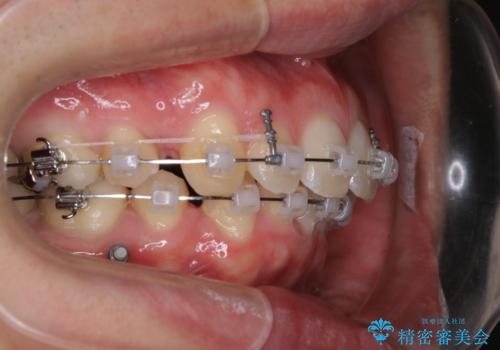

- 矯正装置

- ワイヤー矯正 審美装置

移動量が大きいこと、また、患者さんの生活習慣的にマウスピース装着が難しそうとの理由から

ワイヤー表側矯正装置で治療を行うことになりました。